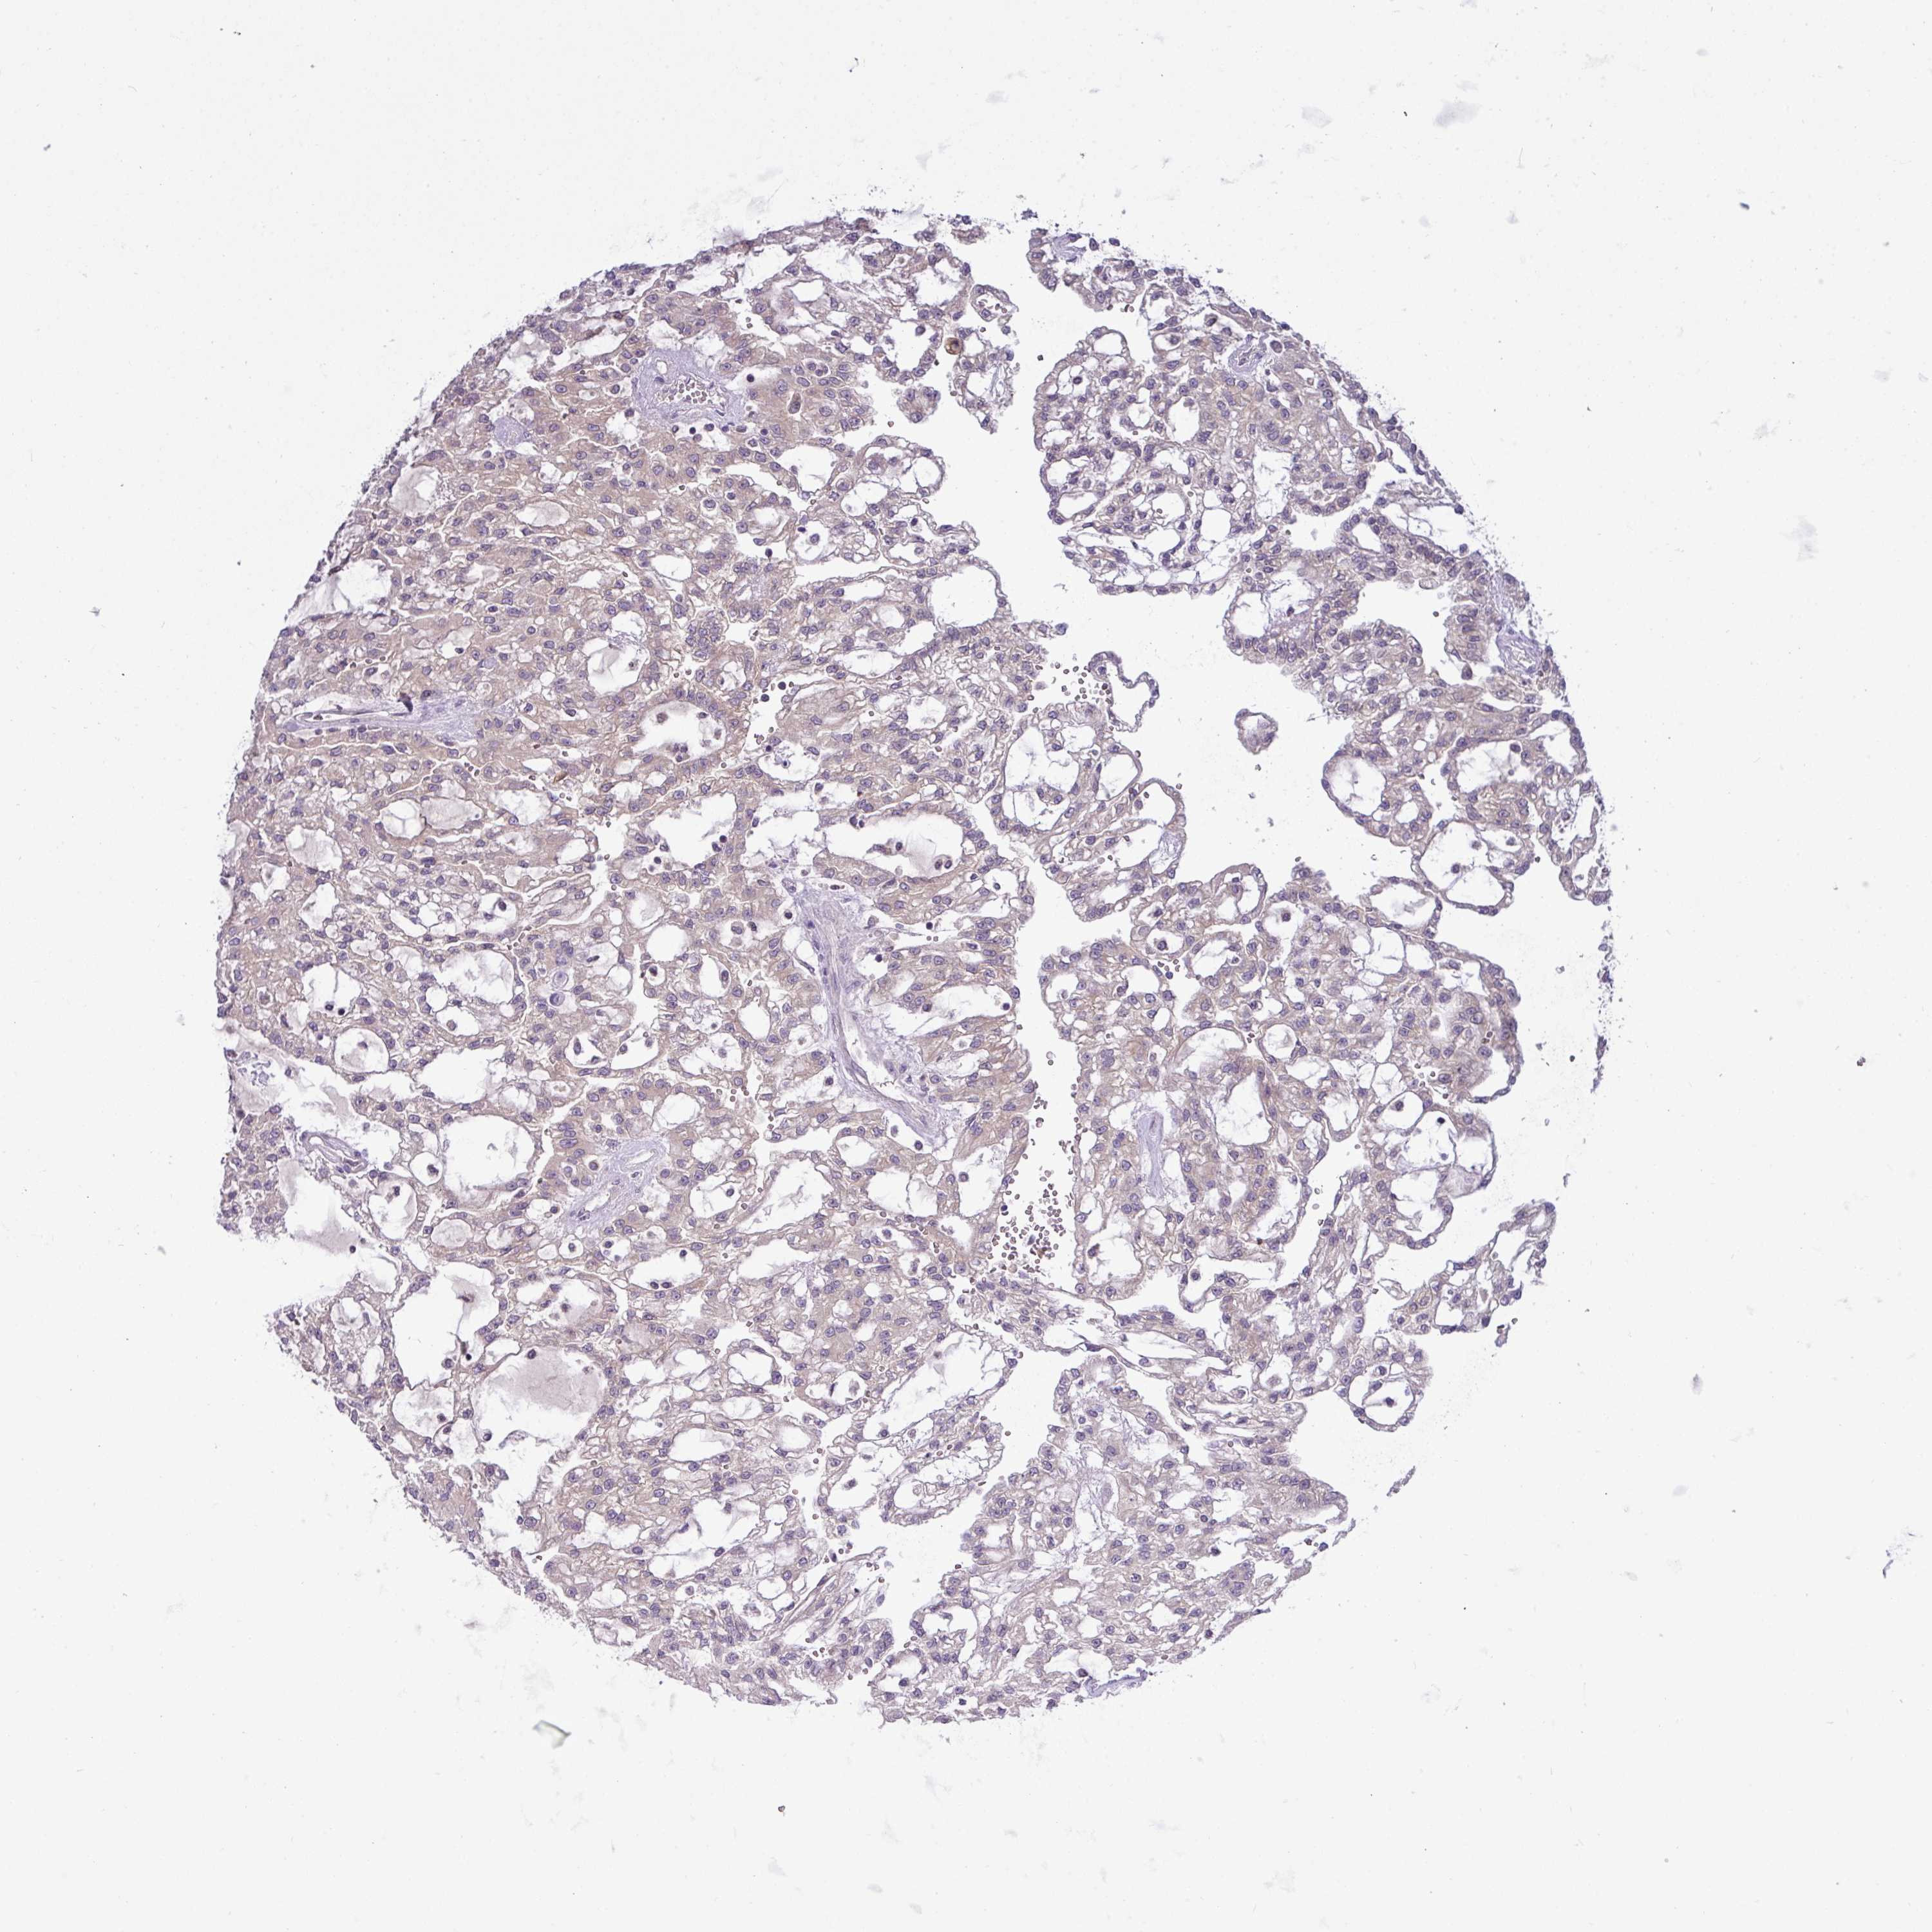

KIDNEY RENAL CLEAR CELL CARCINOMA (TCGA) - Interactive survival scatter ploti

The Survival Scatter plot shows the clinical status (i.e. dead or alive) for all individuals in the patient cohort, based on the same data that underlies the corresponding Kaplan-Meier plots. Patients that are alive at last time for follow-up are shown in blue and patients who have died during the study are shown in red.

The x-axis shows the expression levels (FPKM) of the investigated gene in the tumor tissue at the time of diagnosis. The y-axis shows the follow-up time after diagnosis (years). Both axes are complimented with kernel density curves demonstrating the data density over the axes. The top density plot shows the expression levels (FPKM) distribution among dead (red) and alive patients (blue). The right density plot shows the data density of the survived years of dead patients with high and low expression levels respectively, stratified using the cutoff indicated by the vertical dashed line through the Survival Scatter plot. This cutoff is automatically defined based on the FPKM cutoff that minimizes the p-score. The cutoff can be changed by dragging the vertical line or by entering a cutoff value in the square labeled "Current cut-off".

Under the Survival Scatter plot the p-score landscape (black curve; left axis) is shown together with dead median separation (red curve; right axis). Dead median separation is the difference in median mRNA expression between patients who have died with high and low expression, respectively. It is calculated as follows: median FPKM expression of dead patients with high expression - median FPKM expression of dead patients with low expression. This is intended to aid the user in visually exploring custom cutoffs and the associated p-scores and dead median separation.

& Survival analysisi

Kaplan-Meier plots summarize results from analysis of correlation between mRNA expression level and patient survival. Patients were divided based on level of expression into one of the two groups "low" (under cut off) or "high" (over cut off). X-axis shows time for survival (years) and y-axis shows the probability of survival, where 1.0 corresponds to 100 percent.

TMEM62 is potential prognostic, high expression is favorable in Kidney Renal Clear Cell Carcinoma (TCGA)

: 5.42

Average pTPM 9.0

Number of samples 521